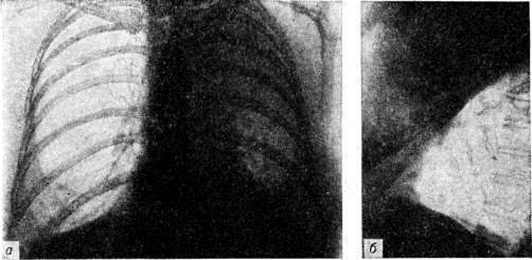

По локализации и объёму поражения лёгких различают следующие формы Пневмония: долевую, или лобарную, Пневмония— при поражении целой доли лёгкого (в этом случае применяют термин «крупозная пневмония»); очаговую Пневмония— при поражении части сегмента, целого сегмента или нескольких сегментов лёгких. В связи с тем, что при очаговой Пневмония обычно поражаются и бронхи, в качестве синонима используется термин «бронхопневмония». Воспалительный процесс при очаговой Пневмония чаще локализуется в нижних долях лёгкого, особенно справа, иногда бывает двусторонним. В случае слияния ряда очагов создаётся впечатление о поражении целой доли (цветной рисунок 1), что обозначается термином псевдолобарная Пневмония (например, при Пневмония, вызванной палочкой Фридлендера). При локализации патологический изменений в строме лёгкого Пневмония называют интерстициальной или межуточной; такие изменения, однако, редко бывают воспалительными в полном смысле слова, как правило, это лимфогистиоцитарно-плазмоцитарные, чаще периваскулярные и перибронхиальные инфильтраты, являющиеся местным проявлением иммунологический реакций. При поражении в основном респираторных отделов лёгких патологоанатомически выделяют альвеолиты — форму Пневмония, характеризующуюся выраженными изменениями альвеолоцитов.

Рис. 1. Макропрепарат лёгкого при пневмонии, вызванной палочкой Фридлендера, стрелками указаны сливающиеся очаги в верхней доле лёгкого (псевдолобарная пневмония).